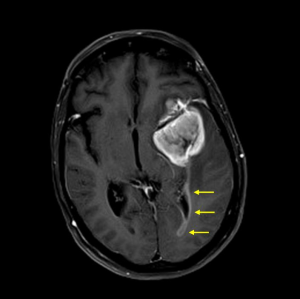

Die Klassifikation der Weltgesundheitsorganisation (WHO) beinhaltet mehr als 130 verschie-dene Tumorarten, die das Gehirn, das Rückenmark oder das periphere Nervensystem be-treffen können. Zu den häufigsten Tumoren gehören die Gliome, die im Gehirn selbst wach-sen (Abbildung 1), Meningeome, die von den Hirnhäuten ausgehen und von aussen das Ge-hirn komprimieren (Abbildung 2), Metastasen («Absiedlungen»), die von ausserhalb des Nervensystems wachsenden Tumoren über die Blutbahn in das Gehirn streuen, und Tumo-ren der Hirnanhangsdrüse (Hypophysentumoren). Je nach Verhalten unterscheidet die WHO vier Tumorgrade, wobei Grad I häufig durch ein langsames (z.B. Meningeom), Grad IV durch sehr aktives Wachstum charakterisiert ist (z.B. Glioblastom).

Die von Hirntumoren verursachten Symptome sind charakteristisch für die Gehirnregion, in der ein Tumor wächst. Frühe Anzeichen können allerdings so unspezifisch sein, dass sie nicht mit einer Tumorkrankheit in Verbindung gebracht werden. Kopfschmerzen kommen in ca. 30% vor. Häufig treten epileptische Anfälle, Lähmungserscheinungen und Sprach- oder Sehstörungen auf. Bei Verdacht auf das Vorliegen eines Tumors wird als wichtigster diag-nostischer Schritt eine Magnetresonanztomographie erforderlich (MRI, Schnittbilduntersu-chung, Abbildungen 1–2). Zur Klassifikation des Tumors muss das Tumorgewebe mikrosko-pisch untersucht werden. Hierzu wird eine Operation erforderlich. Zur Vorbereitung eines möglichst schonenden Eingriffs können wichtige Funktionsareale des Gehirns mittels funktio-neller Magnetresonanztomographie (fMRI) und Darstellung der Nervenbahnen (MRI mit «Fi-ber-Tracking») abgebildet werden. Die Operation wird je nach Lage des Tumors entweder als Gewebeentnahme (Biopsie) oder als Tumorentfernung durchgeführt. Zur Optimierung einer Tumorentfernung werden während der Operation Neuronavigation und Fluoreszenz-Techniken (5-ALA) eingesetzt, um auch kleine Tumoranteile zu identifizieren. Ergänzende molekulargenetische Untersuchungen des Gewebes können darüber Aufschluss geben, wel-che Aussicht auf ein Ansprechen eines Tumors auf weitere Behandlungsmethoden (z.B. Chemotherapie) besteht. Bei Vorliegen von Hirnmetastasen muss zusätzlich nach einem Tumor ausserhalb des Gehirns gesucht und die Behandlung der Hirnmetastasen mit dem gesamt-onkologischen Konzept abgestimmt werden.

Tumorzellart, Ausmass der operativen Tumorentfernung und Zustand des Patienten ent-scheiden darüber, ob weitere tumor-gerichtete Behandlungen erfolgen müssen, oder ob die Tumornachsorge geplant werden kann. Meningeome, die im Bereich der Tumoransatzstellen an den Hirnhäuten vollständig entfernt werden können, sind oft bereits durch eine Operation geheilt. Gliome, die zum Zeitpunkt der Entdeckung häufig Tumorzellwanderung in das um-gebende Gehirn zeigen (Abbildung 1), lassen sich durch eine Operation alleine nicht kontrol-lieren und benötigen weitere tumor-gerichtete Massnahmen. Hierzu stehen je nach Tumorart und -Stadium Strahlentherapie und verschiedene Formen von Chemotherapie zur Verfü-gung. Diese Therapien werden häufig sehr gut vertragen und schränken die Lebensqualität oft nur wenig ein. Die Prognose einer Hirntumorkrankheit ist individuell sehr verschieden und hängt von zahlreichen Faktoren ab (Tumorart und -grad, Alter, körperlicher Zustand, geneti-sche Tumoreigenschaften).

Abbildung 2: Meningeom. Das MRI zeigt, wie der Tumor von der Hirnhaut ausgehend (Pfeile) das Gehirn von aussen komprimiert. |